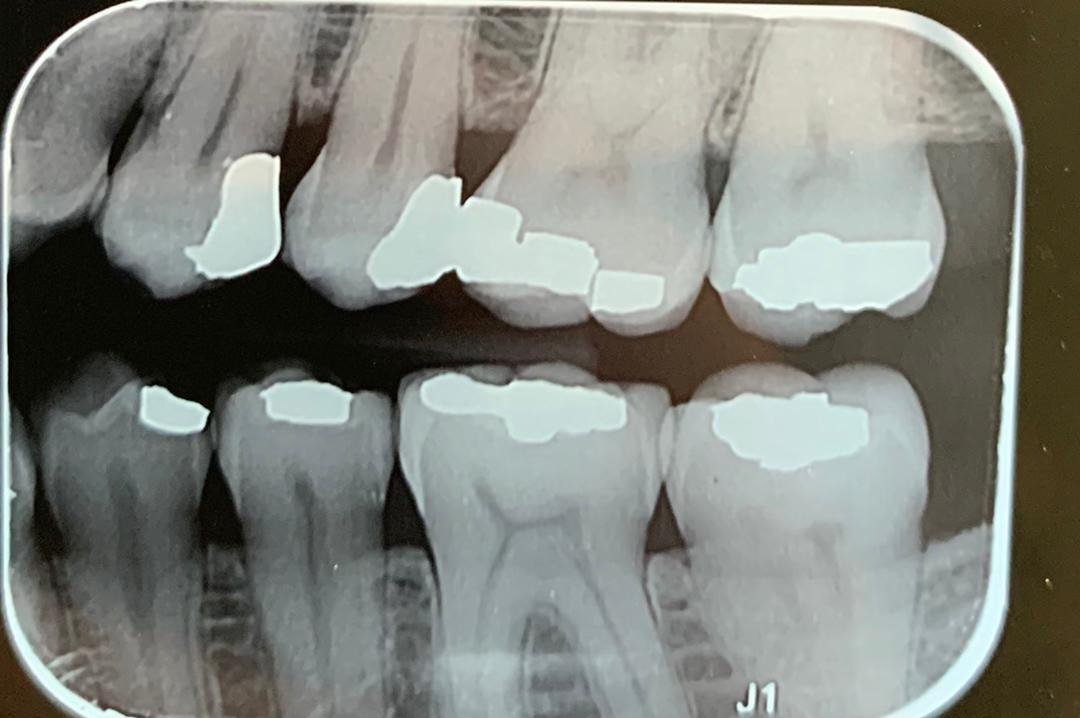

14. Which surfaces shows recurrent caries?

15. Which surface shows recurrent caries?

16. What are the caries level in mesial and distal surfaces of the tooth # 4.6 respectively?

17. What is the Caries level on distal surface of the tooth # 3.5?

18. Which surfaces need restoration?